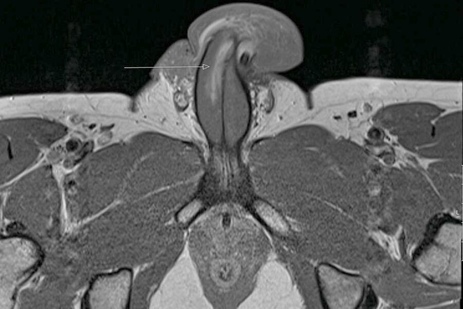

- МРТ: безопасный и эффективный способ получения информации о характере повреждения. При помощи магнитного излучения высокой частоты, доктор получает всесторонние проекции необходимой анатомической области.